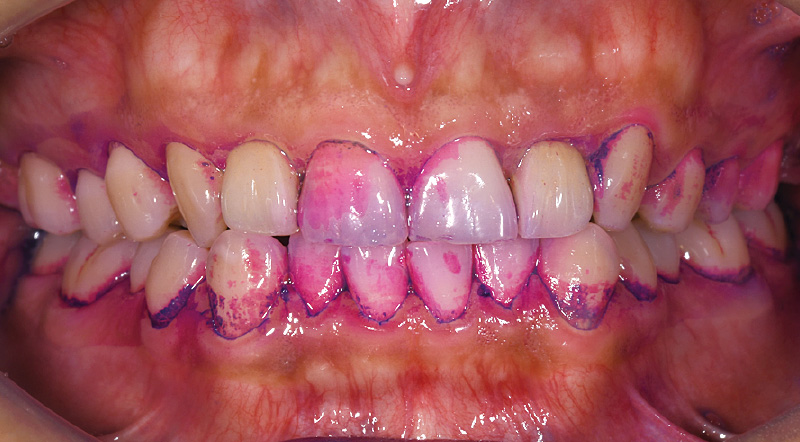

ソニッケアーの旧製品を自己流で使用。ゴシゴシと大きく動かしながら磨いていたため、「ソニッケアー6100」の導入を機に、ブラシを手磨きの感覚で動かさないことや正しい角度を鏡を見ながら丁寧に指導。2週間後には磨き残しが減るなど、改善傾向が認められました。

![[写真] 初診時の染め出しの状態](/academic/dentalmagazine/wp-content/uploads/sites/2/2026/04//196-12_photo07.jpg)

症例2-1 初診時の染め出しの状態。ソニッケアー旧製品を自己流で動かしながら磨いていた。 -